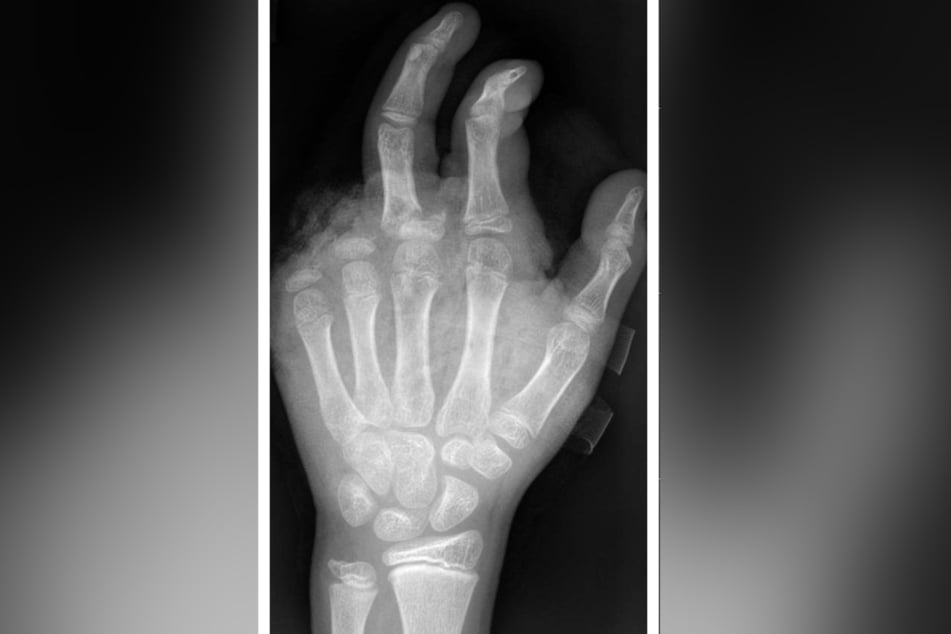

Berlin - Abgetrennte Finger, durchtrennte Sehnen, Amputationen - die Handchirurgin Leila Harhaus-Wähner (45) hat in der Silvesternacht schon vieles gesehen.

In der Handchirurgie müssten an Silvester im Unfallkrankenhaus rund 20 bis 40 Menschen mit Böllerverletzungen operiert werden, sagt die Ärztin. Dieses Jahr werde sie mir vier weiteren Handchirurgen im Einsatz sein. Die häufigsten Verletzungen entstünden durch explodierende Böller in der Hand.

"Der überwiegende Teil der Verletzungen trägt tatsächlich lebenslange Folgen mit sich, weil die Sprengkraft dazu führt, dass eben nicht nur einzelne Strukturen verletzt sind, sondern immer mehrere. Und das heilt praktisch nie ganz folgenlos ab." Zum Teil könnten Hände nicht mehr gerettet und müssten amputiert werden.